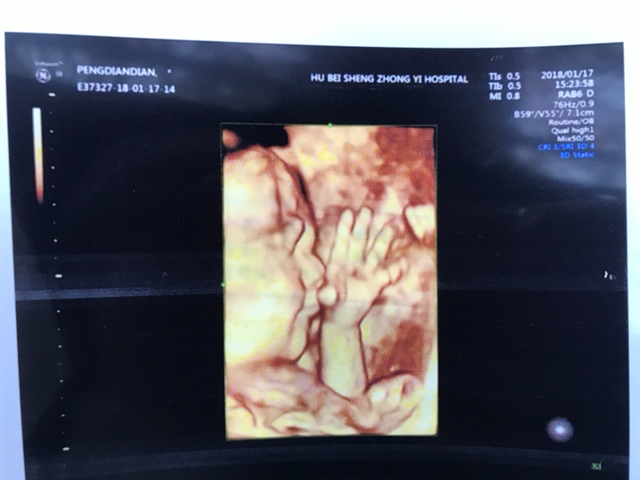

孕30周+6天

好大的手可爱

好可爱,手指头很长呢😘😘😘

MEGBaby_[帖主]:感觉肉乎乎的 萌萌哒